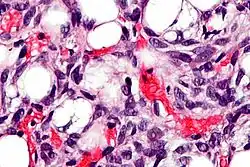

Lipoblastos (flecha blanca) y adipocitos (flecha negra), en un caso de lipoblastoma

Los lipoblastos pueden verse en los liposarcomas[5] y característicamente tienen un citoplasma abundante, claro y multivacuolado y un núcleo mellado y con tinción oscura (hipercromático).